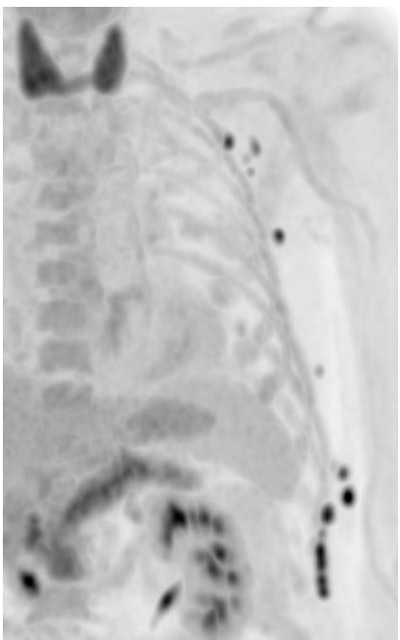

In a patient with malignant melanoma, Rominger and his colleagues artificially reduced the acquisition time down to 30 seconds and managed to image tiny lymph nodes. "We don't miss any small hypermetabolic metastases. In such short scans, image quality becomes worse and noise is increasing, but you could theoretically work with these scans."

The team also imaged a neuroendocrine tumor in a two-minute acquisition scan. "Image quality is very nicely preserved," he said.

Long axial field-of-view (LAFOV) technology is also interesting in children, as it enables the reduction of dose drastically, said Rominger, who shared the example of an eight-year-old child with Morbus Hodgkin disease and cervical, bone, and splenic involvement.

"The child underwent chemotherapy and we reduced the dose down to 14 MBq, so 0.5 MBq per kilo. We obtained very nice corresponding reconstruction and preserved image quality," he said.